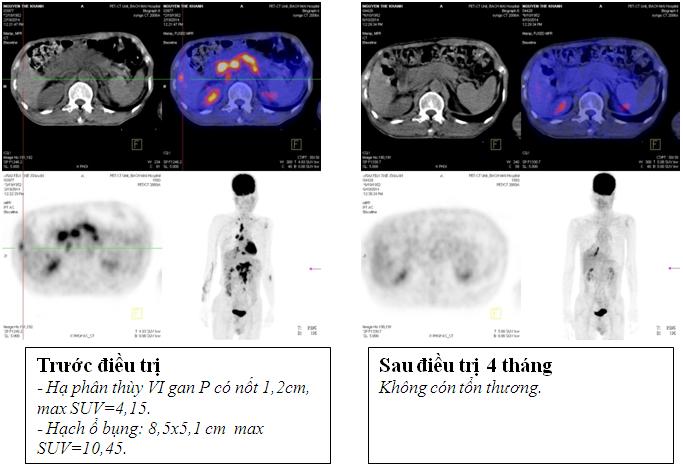

Kết quả chụp PET/CT: Khối vùng phế quản gốc phải KT 2,4x1,7cm; maxSUV=8,50; Hạch dưới carina KT 3,1x3,5cm ; maxSUV=8,50;Nhiều hạch ổ bụng dọc theo ĐMchủ bụng tạo thành khối lớn KT 8,5x5,1cm và 5,1x3,9cm, tăng hấp thu F-18 FDG, maxSUV=10,45; Hạch thượng đòn phải KT 1,1cm, tăng hấp thu F-18 FDG, max SUV=5,67; Hạch thượng đòn trái KT 0,8cm, max SUV=3,97; Tổn thương cung sau xương sườn số 2 bên phải tăng hấp thu F-18 FDG, max SUV=3,13; Nhu mô gan hạ phân thùy VI có nốt KT 1,2cm, tăng hấp thu F-18 FDG, max SUV=4,15.

Đánh giá kết quả sau 4 tháng điều trị: